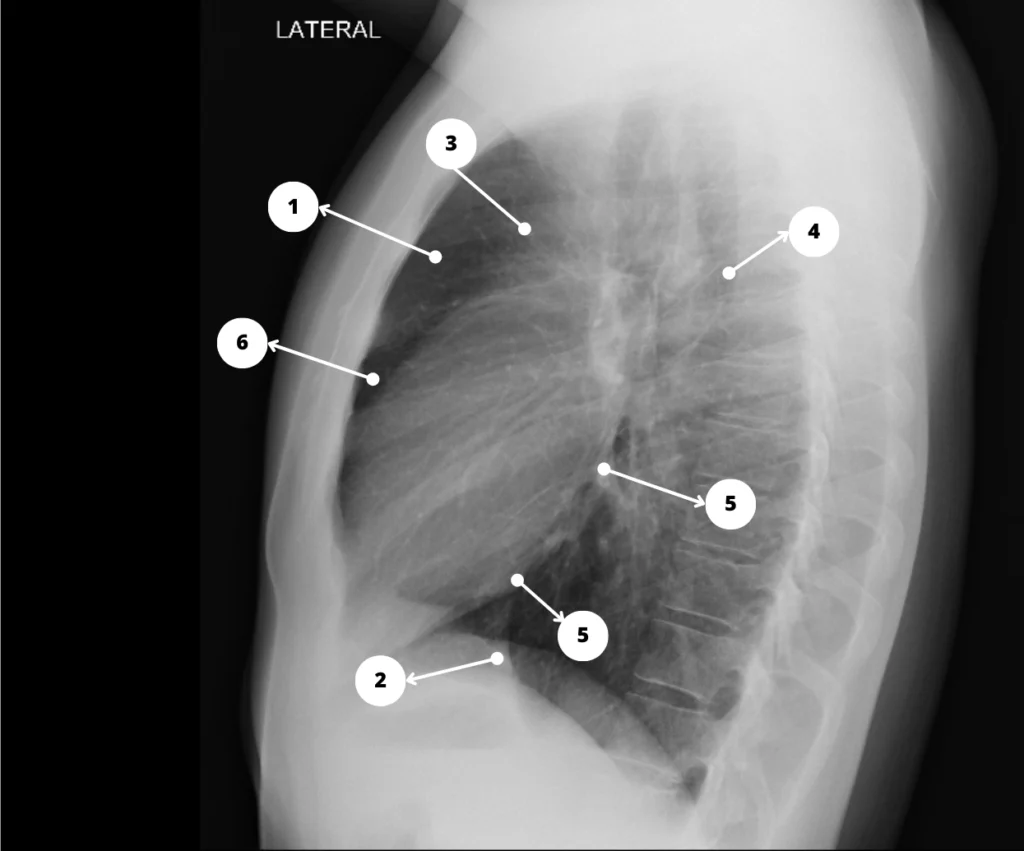

Mediastino en la Rx de tórax L – 1. Espacio claro retroesternal; 2. Ventrículo derecho; 3. Aorta ascendente; 4. Aorta descendente; 5. Aurícula izquierda; 6. Ventrículo izquierdo; 7. Vena cava inferior.

La radiografía de tórax muestra contornos cardiomediastínicos normales. No se identifica masa pulmonar ni pleural.

Una comprensión profunda de las estructuras que normalmente contribuyen al contorno cardiomediastínico es esencial para poder interpretar las radiografías de tórax y localizar anomalías.